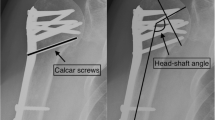

Surgical treatment was performed as described in the surgical technique guides for PHILOS™ and PHILOS™ Augmentation with the use of a deltopectoral approach [31, 32]. Leakage tests were performed in the augmented group by applying a contrast dye to each screw intended to be augmented. If no leakage into the shoulder joint was detected (i.e., negative leakage test), an injection of cement (≤ 0.5 ml) was performed under image intensifier control [24]. In case of leakage into the joint (positive leakage test), an alternative screw was selected for augmentation. To ensure a relatively homogenous effect of augmentation, each patient in the augmented group must have 2–4 screws augmented.

The primary endpoint was the occurrence of mechanical failure during the first year after treatment. Mechanical failures were defined as loss of reduction (≥ 15° increase of varus malposition and a relative change of ≥ 5 mm of the greater or lesser tuberosity), humeral head impaction (≥ 5 mm difference in the outer plate edge and tangent of the humeral head), screw/plate loosening (any outward movement of screw position), and secondary screw perforation (perforation of 1 or more screws through the humeral head). The final assessment of mechanical failure for each patient was done after the last follow-up visit by two experienced independent reviewers. Radiographs were taken postoperatively and at each follow-up visit. Follow-up radiographs from each patient were compared with their postoperative radiographs to determine whether mechanical failures had occurred. Disagreement between the reviewers was resolved by consensus. The mechanical failure risk within the first year after treatment was compared between the treatment groups.

Radiological outcomes

Radiological outcomes were analyzed using the safety population, defined as all patients who received the PHILOS™ treatment. Anatomical reduction was achieved in 24/35 patients (68.6%) of the control group (1 missing value due to the lack of postoperative radiograph) and in 20/29 patients (69.0%) of the augmented group; there was no statistically significant difference between the groups (p = 0.973). Restoration of medial support was achieved in 22/35 patients (62.9%) of the control group and in 18/29 patients (62.1%) of the augmented group, also with no difference between the groups (p = 0.948).